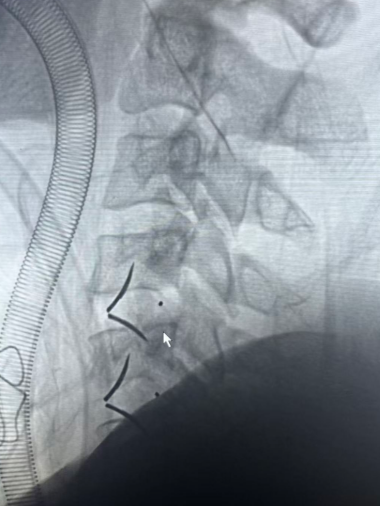

患者取仰卧位,肩部垫高,头自然后仰,顺颈前横纹取颈前横切口,长约3cm,切开皮肤、皮下组织,游离颈阔肌皮瓣,电凝止血,经胸锁乳突肌内侧间隙、颈动脉鞘与气管食管之间的间隙进入椎前,切开椎间筋膜,用定位针标记,C型臂透视定位颈4-5、5-6椎间隙,撑开器撑开颈4-5、5-6椎间隙,生理盐水冲洗下,镜下摘除残留的椎间盘,脊柱内镜探查见左侧椎间盘破裂向后脱出,后纵韧带破裂,一次性无菌磨钻切除椎体后方骨赘及前方椎体,以充分减压,用刮匙去除颈5-6椎间部分软骨板,修整椎间植骨床;清除组织碎片,将自体骨与异体骨混合填充于椎间融合器中,于颈4-5、5-6椎间隙置入Uni-C插片式颈椎自稳定型融合器各1枚,再于颈4-5、5-6椎体前方椎间融合器打入插片各两枚,术中观察及C型臂透视插片及椎间融合器固定良好、位置满意:充分止血,冲洗切口,颈部切口置引流1根,持续负压吸引,逐层缝合,无菌敷料包扎,颈托外固定,术毕。

手术顺利,麻醉满意,术中出血量约20ml,患者生命体征平稳,术后安返病房。

术后透视